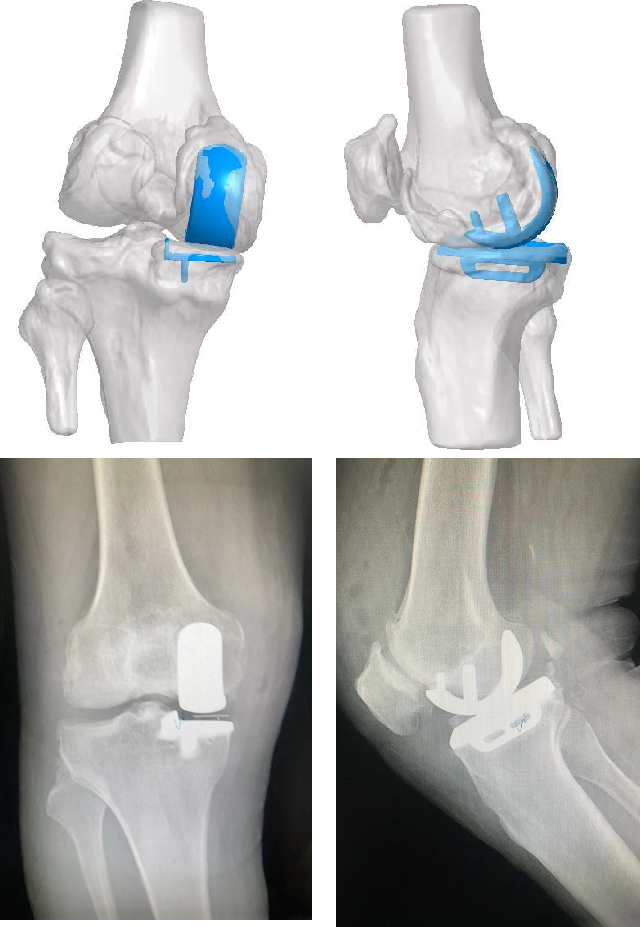

图片

不同案例——导板术中应用